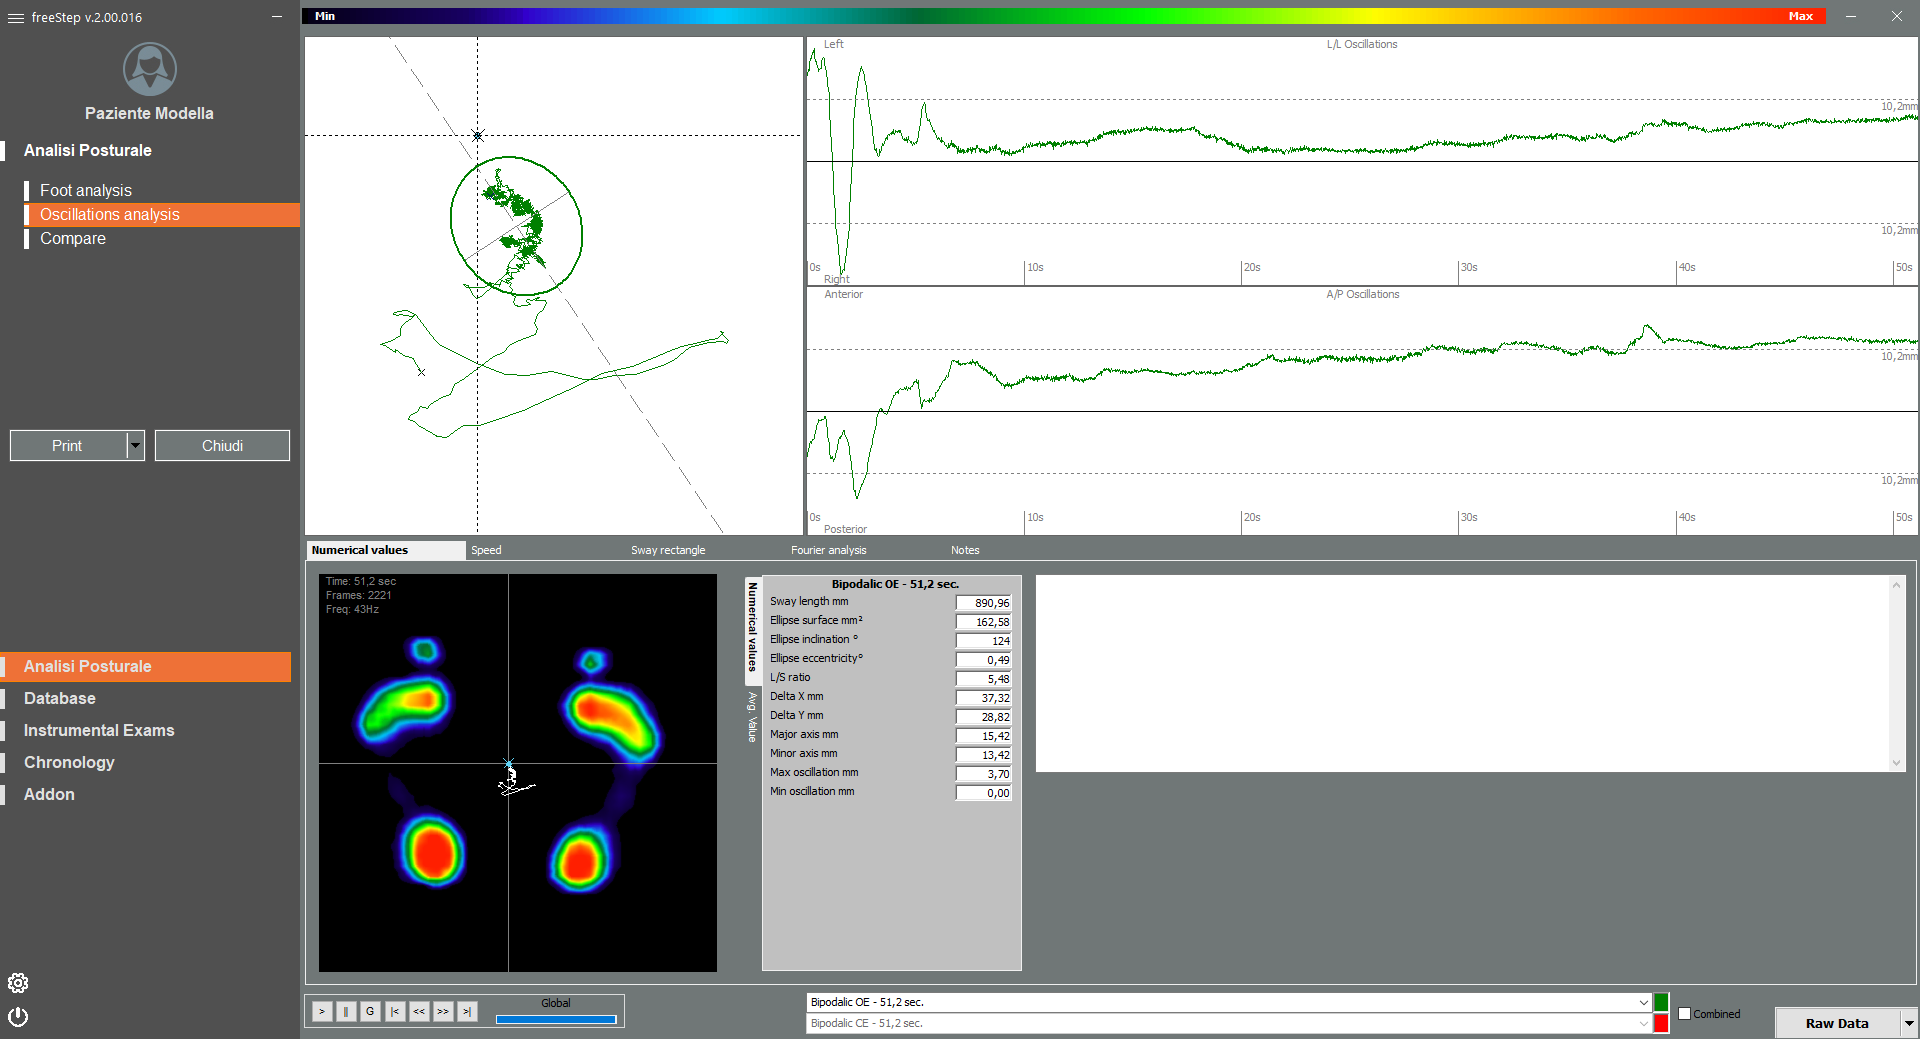

Высокая скорость сбора данных

Частота дискретизации более 400 кадров в секунду для получения детального анализа линии походки и колебаний проекции центра тяжести тела.

- Отклонения центра масс